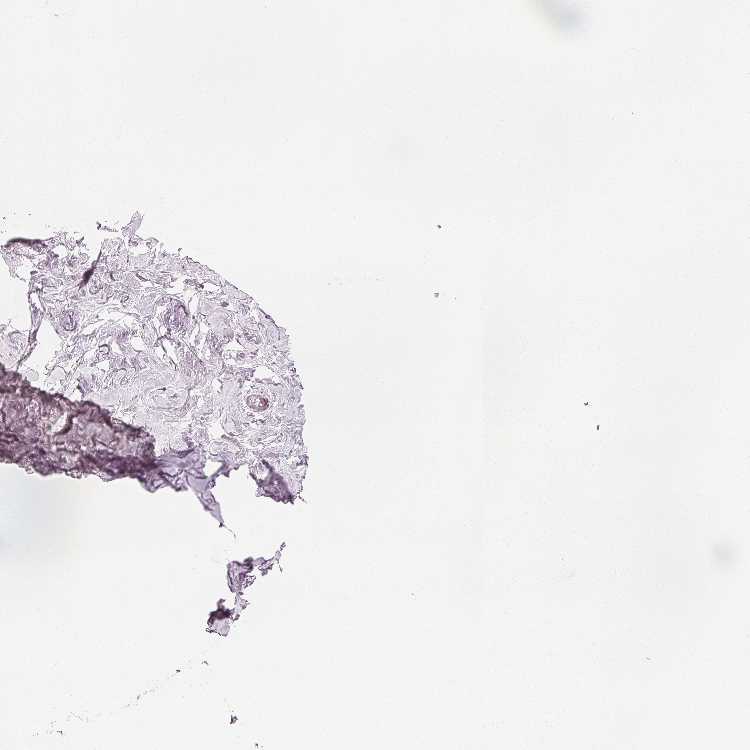

BREAST - Antibody stainingi

Antibody staining in the annotated cell types in the current human tissue is reported as not detected, low, medium, or high, based on conventional immunohistochemistry profiling in selected tissues. This score is based on the combination of the staining intensity and fraction of stained cells.

Each image is clickable and will lead to virtual microscopy that enables deeper exploration of all samples and also displays staining intensity scores, fraction scores and subcellular localization as well as patient and tissue information for each sample.

Antibody HPA023099Antibody HPA056734Antibody CAB002138

Adipocytes Not detectedNot detectedNot detected

Glandular cells Not detectedNot detectedNot detected

Myoepithelial cells Not detectedNot detectedNot detected